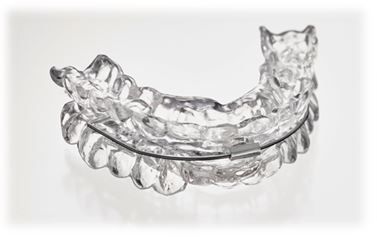

Schlafapnoebehandlung

Bei nachgewiesener Schlafapnoe kann die Anpassung einer Protrusionsschiene erfolgen. Auch die operative Behandlung mittels einer sogenannten Umstellungsosteotomie ist möglich. Die Zusammenarbeit mit anderen Fachdisziplinen ist hier essentiell.